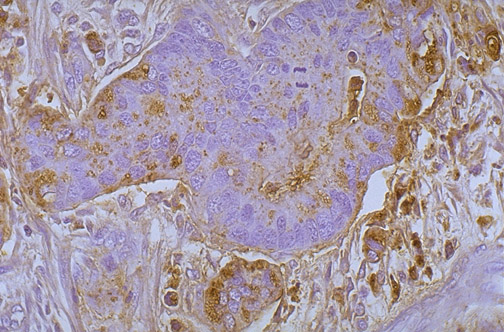

Carcinoembryonic antigen (CEA) positivity is marked in the neoplastic cells of this colonic adenocarcinoma.